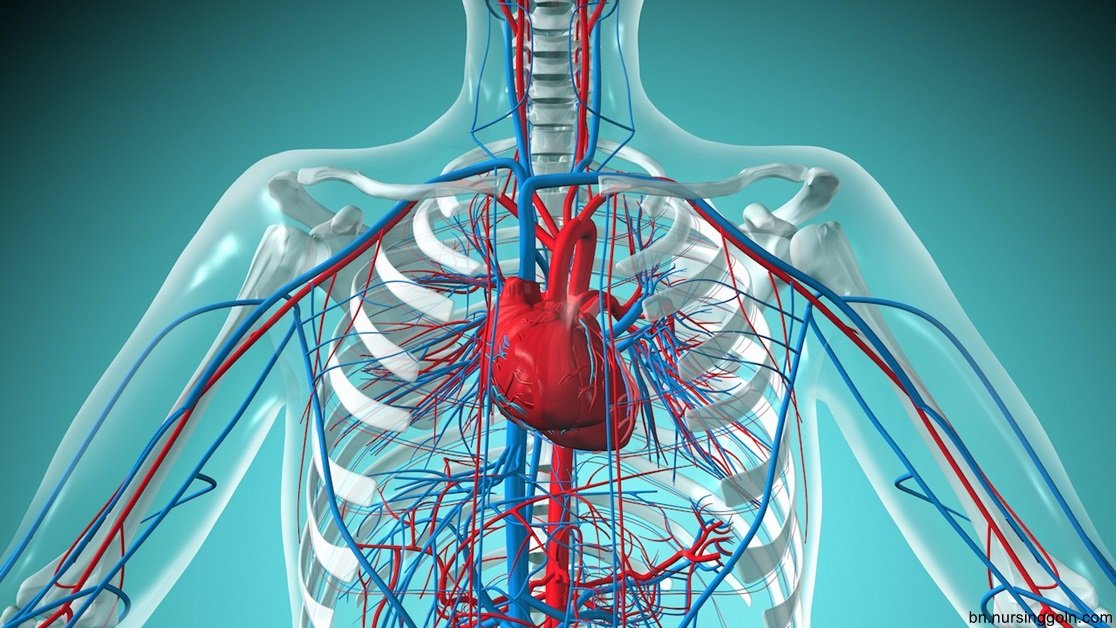

সেবাদানের জন্য মানব শরীর সম্পর্কে সুস্পষ্ট ধারণা থাকা জরুরি। দেহের গঠন, কার্যপ্রণালী, গুরুত্ব, অঙ্গপ্রত্যঙ্গ ও অন্নসমূহের জ্ঞান, সেবা গ্রহণকারীর চাহিদা অনুযায়ী কাজের পরিধি ও পরিকল্পণা করার পূর্ব শর্ত।